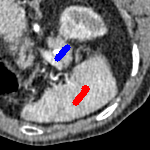

The motivation for this work comes from observing contradictions in using piecewise-constant intensity fitting terms in selective segmentation. Whilst good results are possible with this approach, the exceptional cases lead to severe limitations in practice. This is quite common in medical imaging as demonstrated in Fig. 1, where the target foreground has a low intensity. Given that the corresponding background includes large regions of low intensity, the optimal average intensities for this segmentation problem are and . For cases where , we see that by (1), almost everywhere in the domain . This means that it is very difficult to achieve an adequate result, without an over-reliance on the user input or parameter selection.

| (10) |

for and as defined in (33). This is consistent with respect to the intensities of the observed object and the concept of selective segmentation. In Fig. 3 we see the difference between CV and the proposed fitting terms for given user input on a CT image. For the CT image, the CV fitting terms are near 0 within the target region. This is despite there being a distinct homogeneous area with good contrast on the boundary. This illustrates the problem we are aiming to overcome. With the proposed fitting term this phenomenon should be avoided in cases like this. By defining as in (33) there is no contradiction if the foreground and background intensities of the target region are similar.